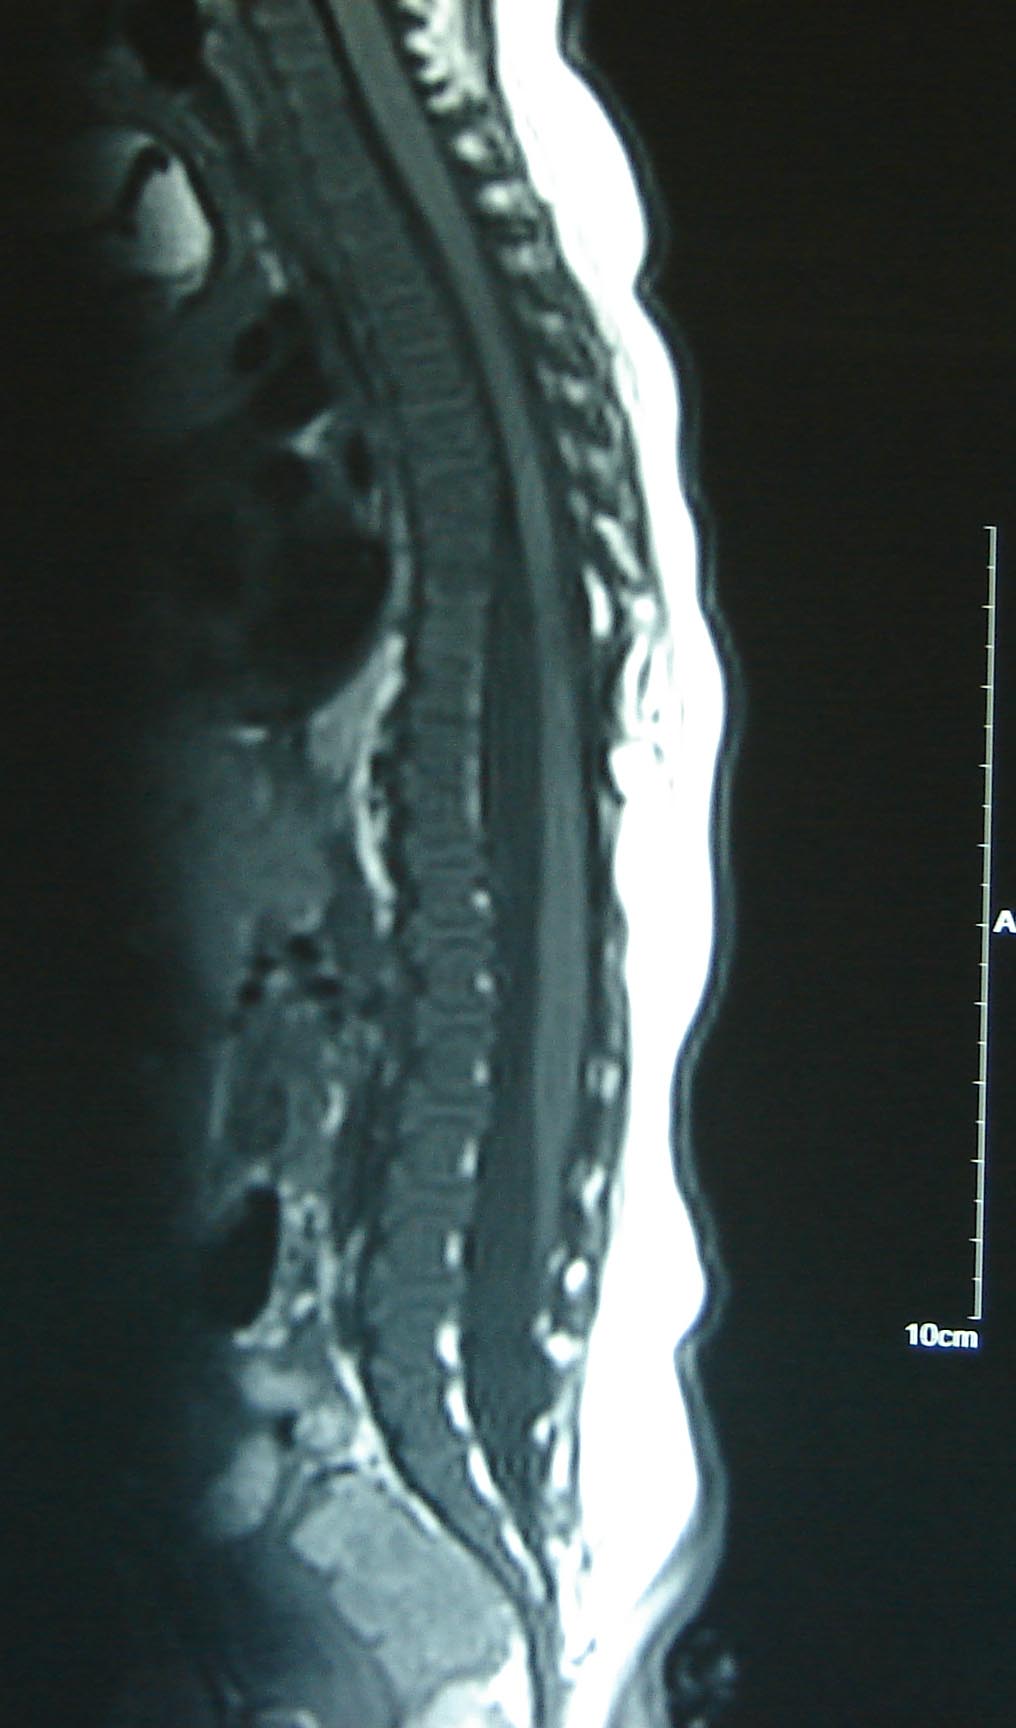

Category: Spinal Dysraphism

Tethered cord syndrome

lpmmc